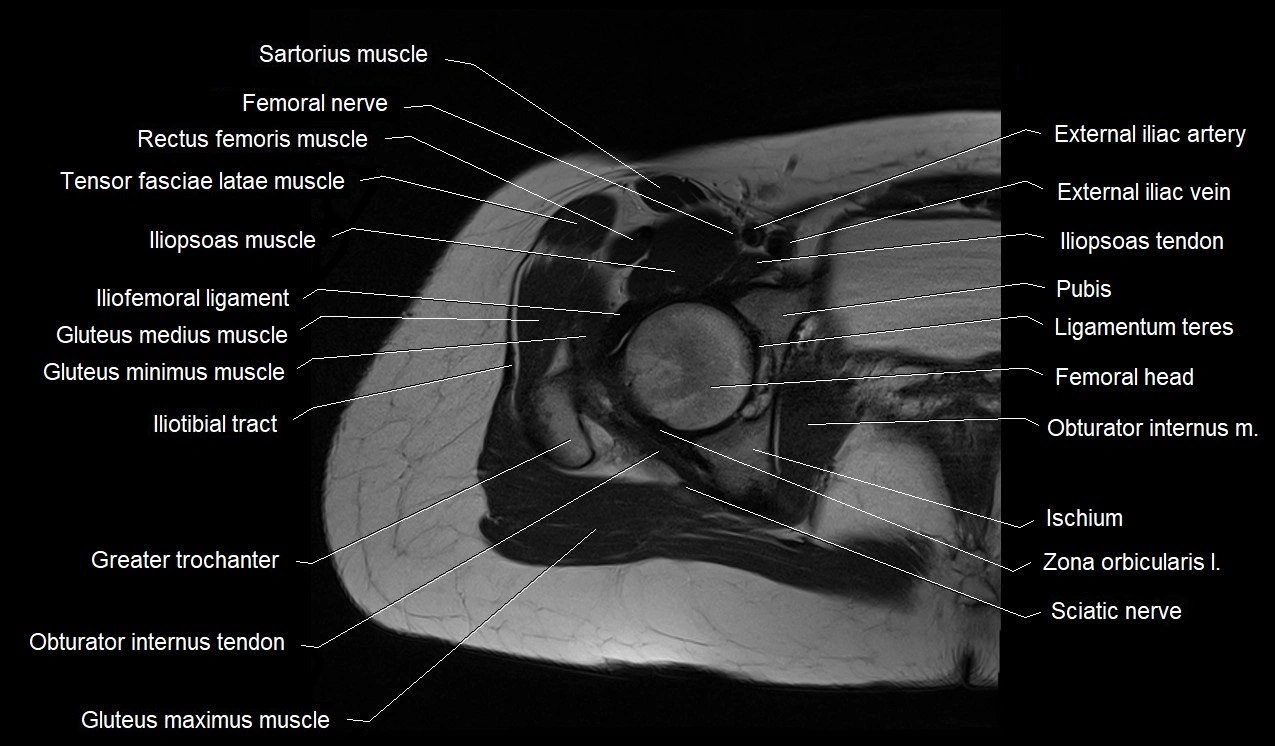

- External iliac artery

- External iliac vein

- Femoral nerve

- Gluteus maximus muscle

- Gluteus medius muscle

- Gluteus minimus muscle

- Greater trochanter

- Iliofemoral ligament

- Iliopsoas muscle

- Iliopsoas tendon

- Iliotibial tract

- Ligamentum teres (ligament of the head of femur)

- Obturator internus muscle

- Zona orbicularis ligament